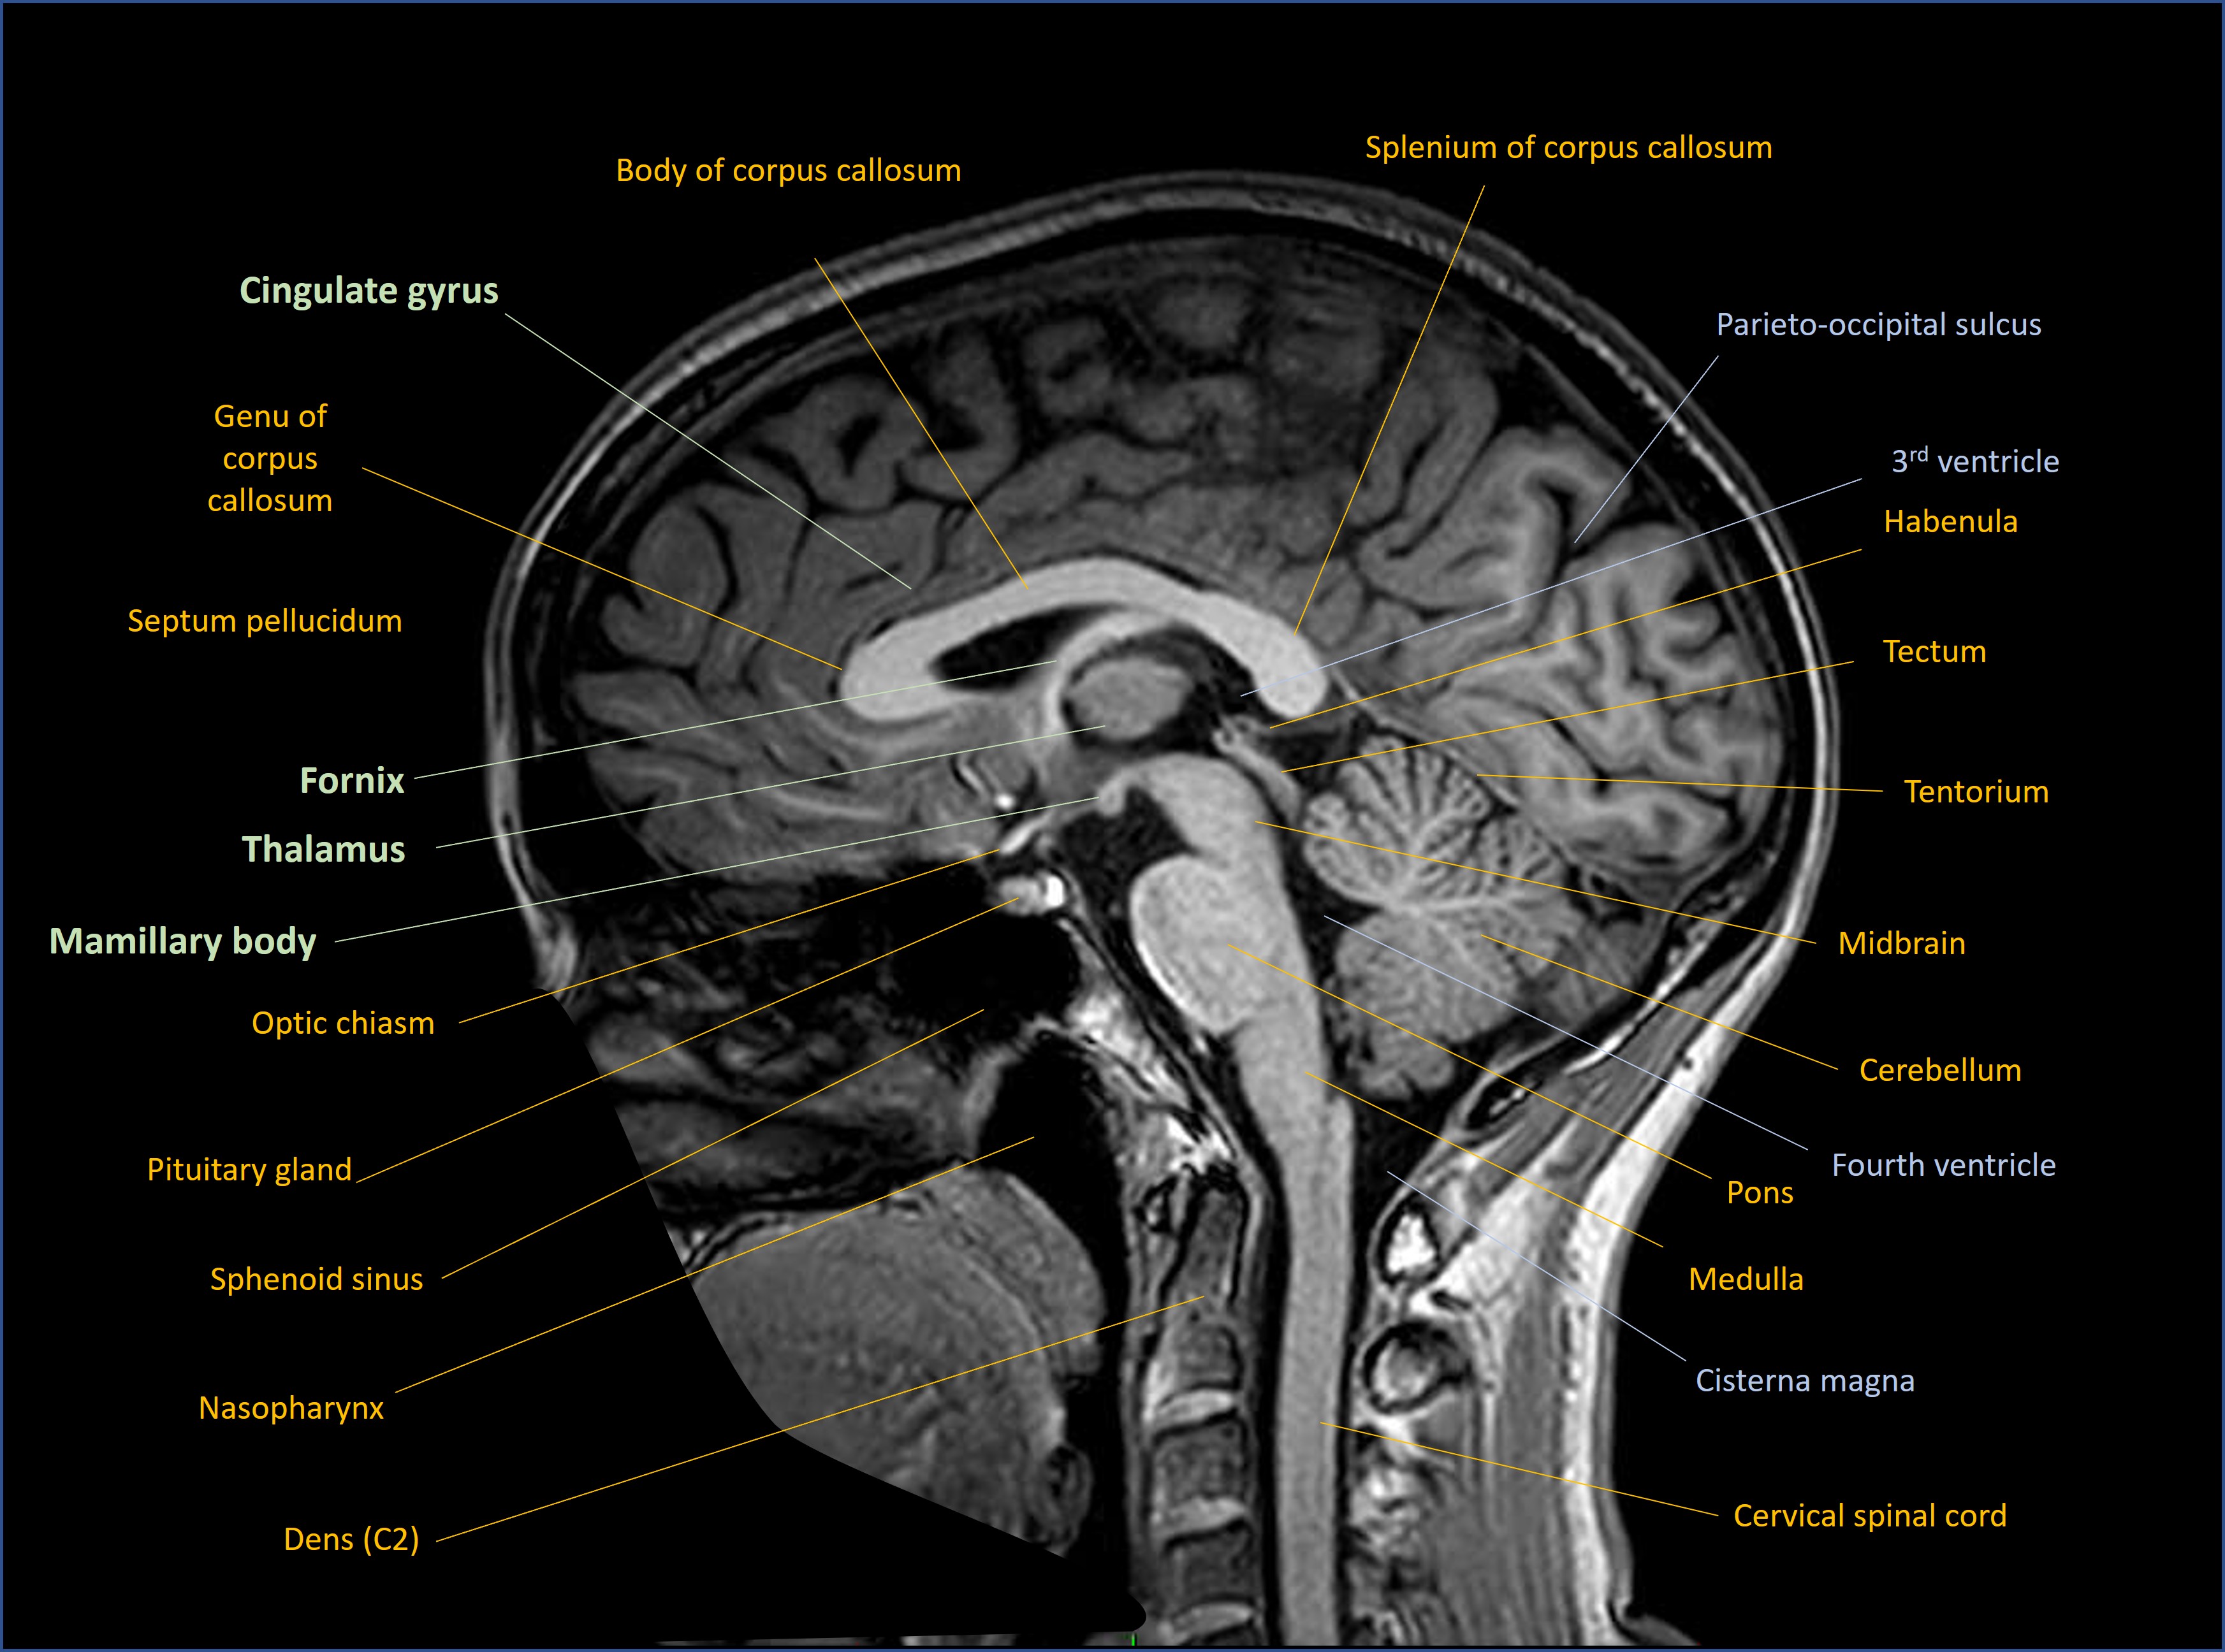

The most famous part of this circuit is the hippocampus - a seahorse-shaped area of cortex. We have two, one in each of the mesial temporal lobes on either side. Note that for the temporal lobe the term ‘mesial’ is generally used rather than ‘medial’. The following scans show the key anatomy in coronal, sagittal and axial views respectively.

Sagittal

The hippocampus sends efferent neurons out into the Papez circuit via the fornix, which is its outflow system. The fornix is a curved structure which is located in each hemisphere. It loops back, up and inward, fusing with its twin from the opposite hemisphere, then travels forward and finally separates into two pillars which drop down again on the front side of the third ventricle. The hippocampal projection fibres from the fornix then synapse in the mamillary bodies on each side.

The mamillary bodies then send mamillothalamic projections to the anterior nuclei of the thalamus, where they synapse. Of note though, there are other parts of the thalamus which are relevant to memory, including the dorsomedial and pulvinar components - lesions there can also produce amnesia.

The anterior thalamus sends fibres out to the cingulate gyrus, above the corpus callosum. The cingulate then returns signal down to the temporal lobes in the parahippocampal gyrus (the entorhinal cortex), and from there it loops back to the hippocampus.